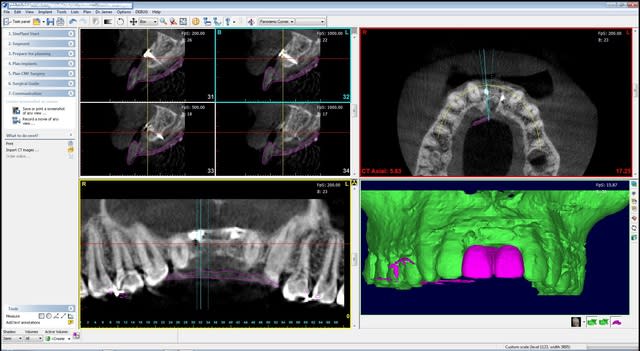

la suite demain matin...

enfin, dans quelques heures...

Pour les non-initiés, mon 57, tes photos sont tres belles, mais ca manque un peu de texte et d'explications, non?. Tu as fait plus didactique!

Sorry D57 , mais il me semble que la pose des implants est tout à fait possible en première intention. la configuration anatomique est tout à fait favorable à une ROG classique sur les implants avec ou sans vis supplémentaire.

pourquoi faire compliqué ?

Je crois bien que tu vas pouvoir faire une petite expansion, sur greffe biobank, il me semble que j'ai déjà vu ça et que ça marche...;-))